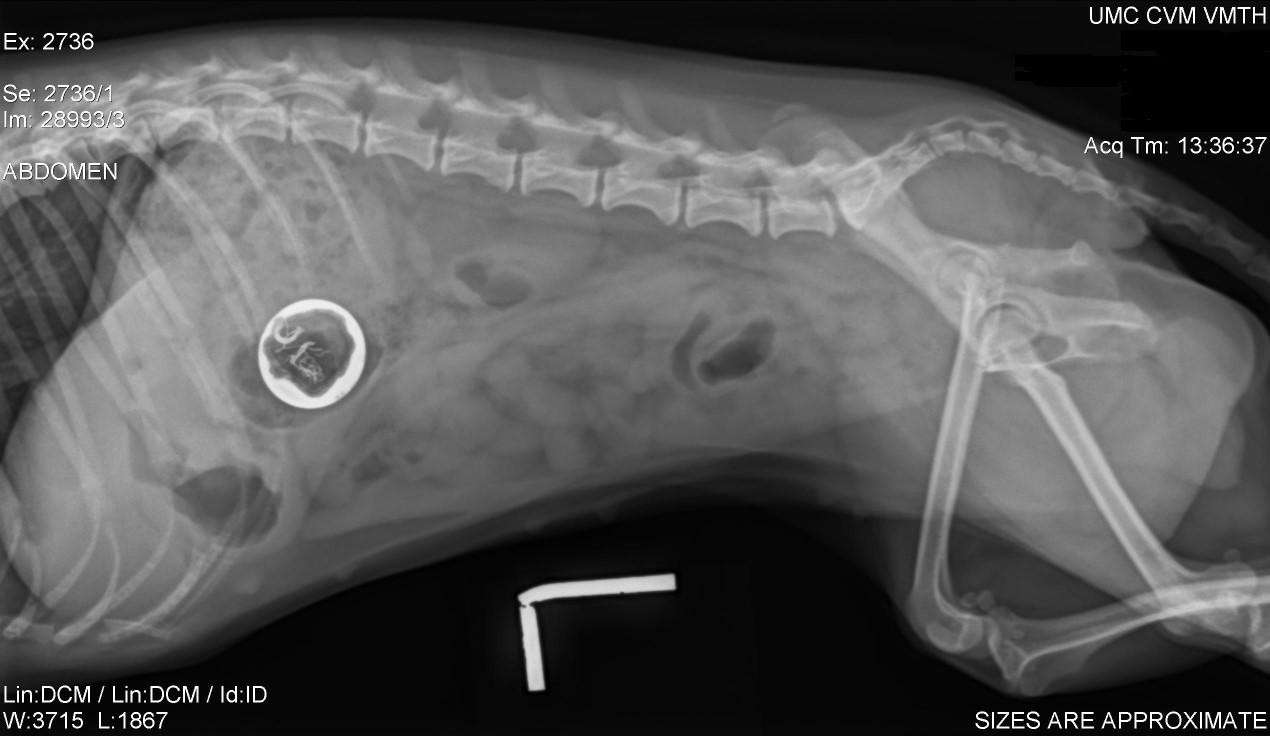

FelineThymomaandThymomalikeDermatosis

History:rapidonsetofscalyskindisease

Lesions:Generalizedscaling,hairloss

Diagnosis:thoracicradiographs;skinbiopsies –apoptotickeratinocyteswithlymphocyte satelitosis;ruleoutinfections,ectoparasites (Cheyletiella)